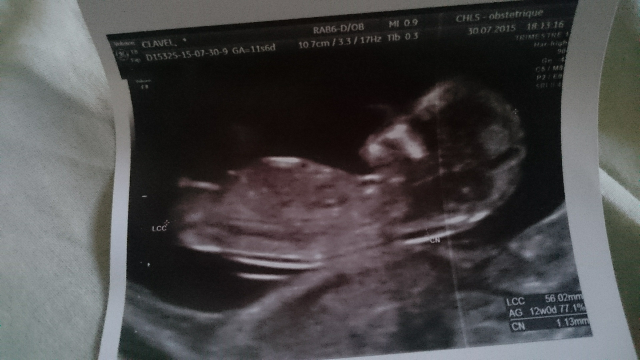

Alors écho qui s'est super bien passé.... Elle l'a mitraillé.

Elle allait pas me parler du sexe mais le tubercule génital était hyper voyant du coup je lui ai demandé son avis et elle elle dirait fille, a confirmer évidemment. Du coup chéri espère que ça soit faux mdr. Enfin bref. Je vs mets la photo qd même ^^ Bébé fait 6cm